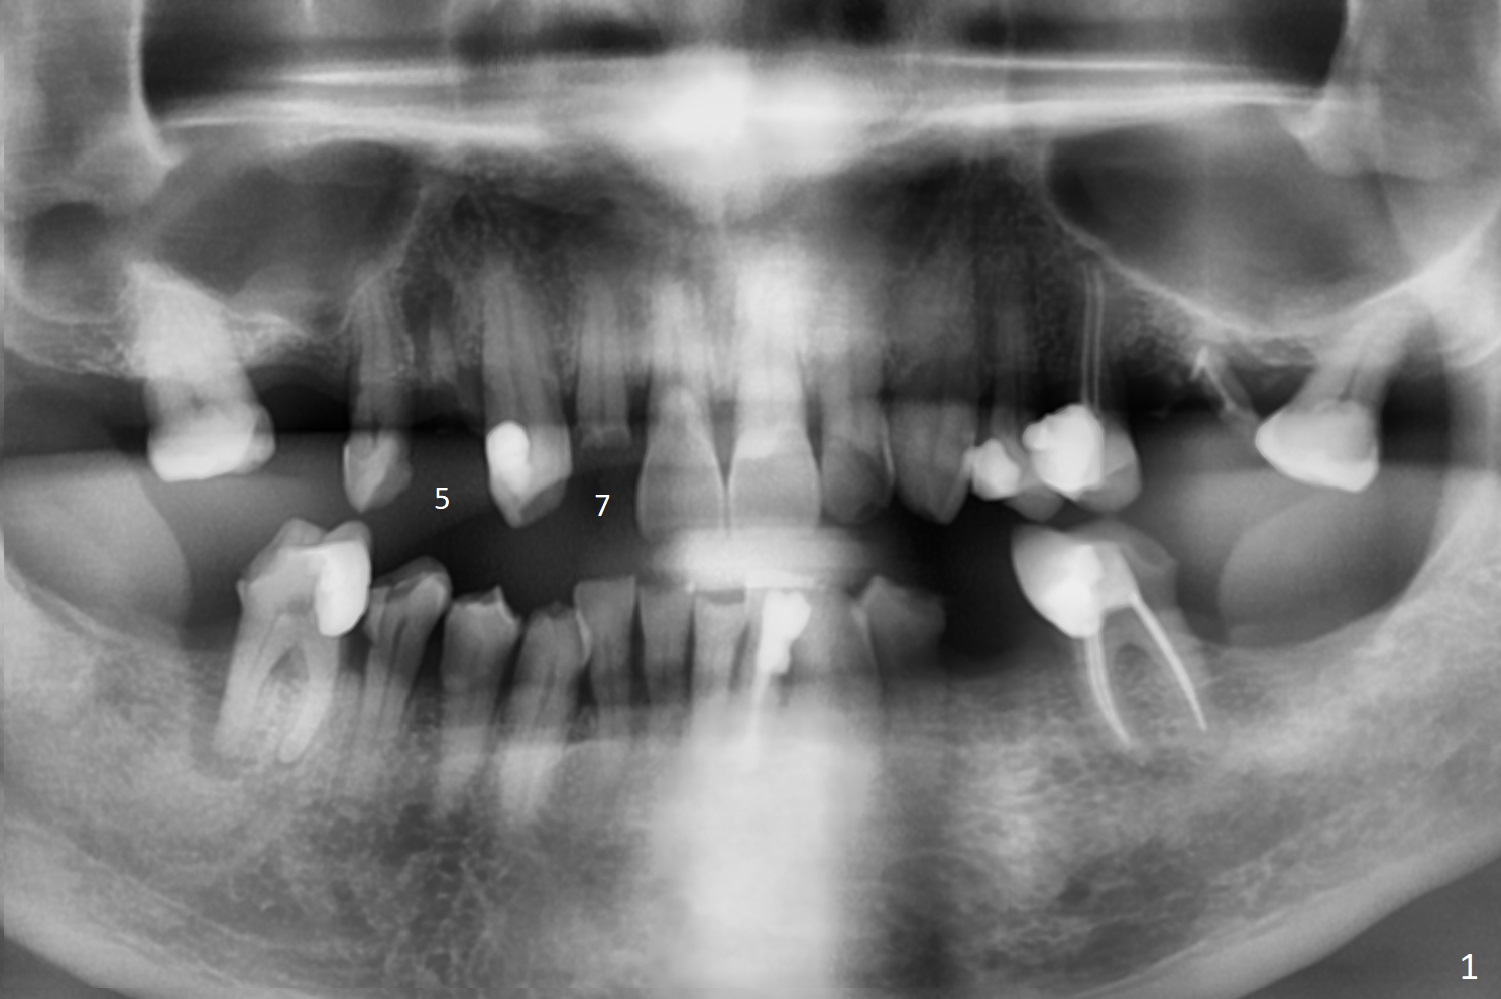

Tooth Fracture as Related to Class V Defect M

A 79-year-old man, who fractured the tooth #7, has several Class V defects (Fig.1). He seems to be a bruxer. Pay attention to occlusion and determine whether he has anterior deep bite. The neighboring tooth, #6, has apical lesion (Fig.2 <). Root canal therapy has been finished prior to implant placement (Fig.3). Prepare Tatum 1-piece implant in case the trajectory is off. If the crown height is more than 10 mm, prepare IS system. Otherwise use DIO one. If the root turns out to be difficult to extract, be ready for socket shield. Preop CT shows minimal apical perforation at #7 (Fig.4 (3-D image)). The buccal plate is thin (Fig.5 (coronal section) between arrowheads (acute infection may increase the perforation quickly)), while the crest is thick (*).